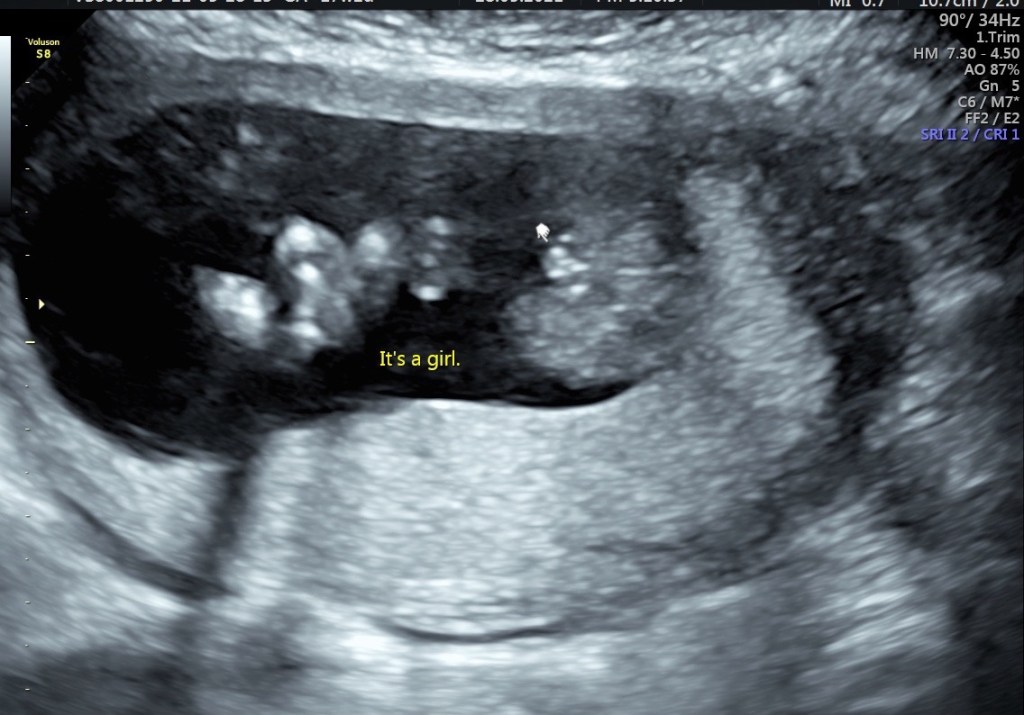

When we went for the scan it was not quite 20 weeks but to our surprise they said they’d be able to tell us the gender if we wanted to know.

As I lay on the table being scanned I looked for any signs of what I was going to be having. The sonographer said there’s these two things here on the screen. What do you think it is, she asked. I thought testes and so did my husband but we both said we didn’t know. To our surprise it was the labia – we were having a girl!